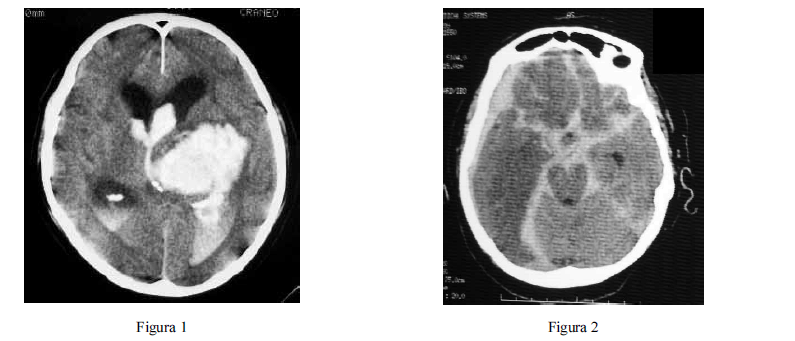

Com relação às figuras 1 e 2 acima, que mostram os exames de imagem de dois pacientes distintos, julgue os itens que se seguem.